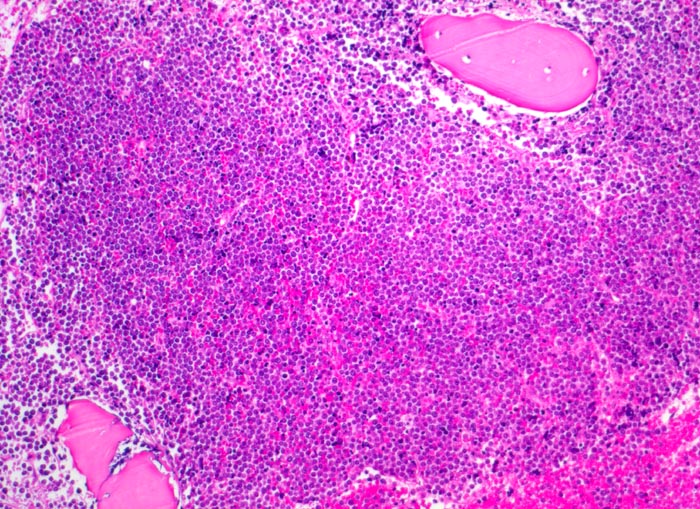

PathoPic – image database / PathoPic ID 4022 - Akute lymphatische Leukämie (ALL)

Akute lymphatische Leukämie (ALL)

Knochenmark, Beckenkamm

Verdrängung des Fettmarkes durch diffuse undifferenzierte Tumorzellrasen. Weitgehende Verdrängung der Myelo-, Erythro- und Megakaryopoese (monotones Bild).

Vergrösserte Lymphknoten, Hepato-Splenomegalie. Knochen- und Gelenkschmerzen, vermehrte Müdigkeit.

Histologie

Vergrösserung

13

männlich